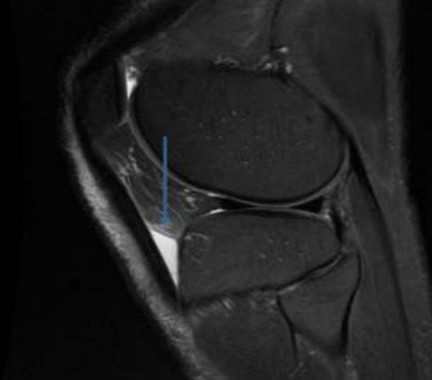

МРТ коленного сустава: сумка расположена под кожей над бугристостью большеберцовой кости (стрелка)

Поверхностный инфрапателлярный бурсит, также называемый коленом священника, возникает из-за воспаления и накопления жидкости в результате хронического сдавления. Клинически наблюдается ощутимая припухлость ниже коленной чашечки. Изначально боль может отсутствовать.

На МРТ патология выглядит как жидкостное образование, выступающее перед сухожилием надколенника (стрелка)

При визуализации бурсит дифференцируют с подкожным отеком, последний представляет диффузное (не локализованное с четкими границами) депонирование жидкости по всей поверхности колена.